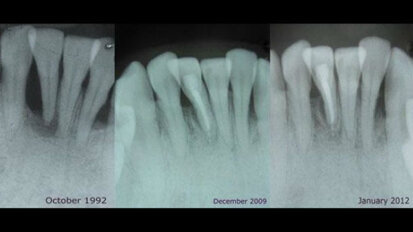

Trattamento estetico-funzionale in un caso di amelogenesi imperfetta generalizzata

Una paziente affetta da amelogenesi imperfetta generalizzata (Figg. 1a, 1b) aveva richiesto in età adulta un trattamento estetico. La paziente ...